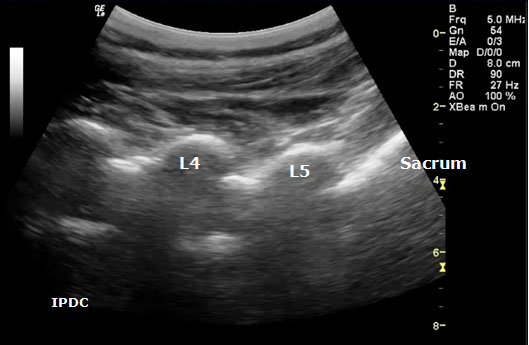

In order to visualize the appropriate structures for lumbar medial branch blocks, a low frequency curved array transducer (2-6 MHZ) is needed.[34] The views utilized to define the sonoanatomy are the cross axis and the long axis views (Figure 11). In the long axis view, the appropriate level of the spine can be identified (Figure 12). The cross axis view demonstrates the step-off deformities between the spinous, superior articular, and transverse processes (Figure 13). In some cases the facet joint between the superior and inferior articular processes can be visualized in the cross axis view. The anatomical landmarks for the L5 dorsal ramus can be difficult to visualize with ultrasound secondary to bony artifact from the iliac crest.

Figure 12. Sonographic long axis view.

Greher et al.[34] developed an ultrasound methodology for the lumbar medial branch block. First, the patient is placed in the prone position with a pillow under their abdomen to reduce the lumbar lordosis. The appropriate level of the lumbar spine is identified under the long axis view, and the level to be anesthetized is centered. The transducer is then rotated 90° to the cross axis view. The step-off deformity is seen between the superior articular process and the transverse process. Under real-time ultrasound guidance with an in plane technique, a 22-gauge spinal needle is inserted from lateral to medial (Figure 13). The insertion angle is approximately 45° to 60° to the skin. The needle is directed down to the junction between the superior articular process and the superior border of the transverse process. Once bony contact is reached the transducer is rotated back to the long axis view to confirm that the needle tip is at the cranial edge of the transverse process. Local anesthetic is then injected to anesthetize the targeted medial branch.